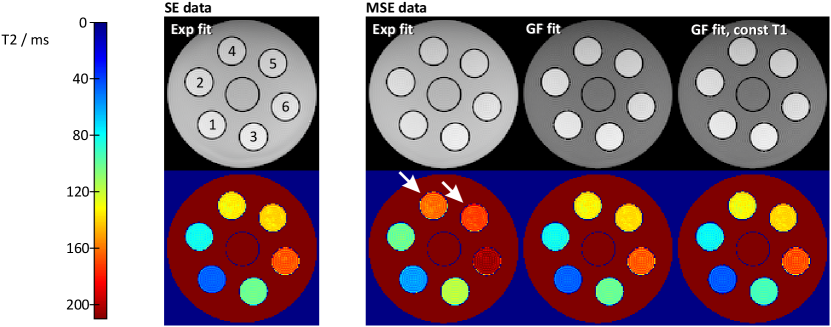

Figure 4

compares spin-density and T2 reconstructions obtained for a fully sampled SE and fully sampled MSE dataset. The results for a pixel-wise mono-exponential fitting of the SE magnitude (measurement time ) serve as a reference (ground truth). On the other hand, the corresponding fitting of the MSE images (first echo removed) yields the expected T2 overestimation in all compartments (arrows). In contrast, the GF fitting of the same data results in T2 values which are remarkably similar to the reference. Deviations in the surrounding water compartment, which are most notable in the spin-density map, are again an effect of the limited frequency domain oversampling (). The quantitative results from a ROI analysis in Table I

confirm the visual impression. The relative error of the GF fit to the reference is or less in all compartments. The mono-exponential fit, on the other hand, yields errors between and .

A practical limitation of the accurate GF fit is the necessity for additional B1 and T1 measurements. However, as has already been pointed out in [12, 21], the influence of T1 on the GF result is relatively small. This finding is confirmed in Fig. 4 (right), where additional reconstructions were performed under the assumption of a constant T1 value of for all pixels. Although the relative error in T2 increases the stronger the chosen T1 deviates from the true value, the results are surprisingly accurate and even for worst cases, the largest error in the T2 map is still lower than the smallest error of the mono-exponential fit.